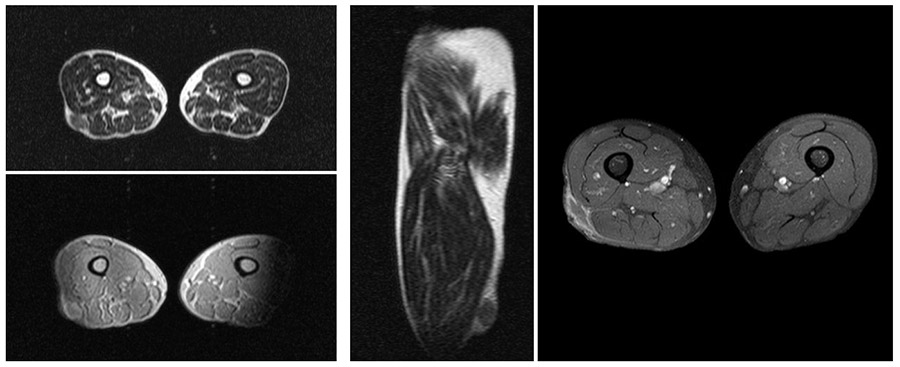

Ameliyat Öncesi: İlk başvuru anında cilt altı yerleşimli düzensiz heterojen kitle ile plansız ameliyat sonrası kalıntı tümör dokusu ve çevreleyen ödem görülmekte.